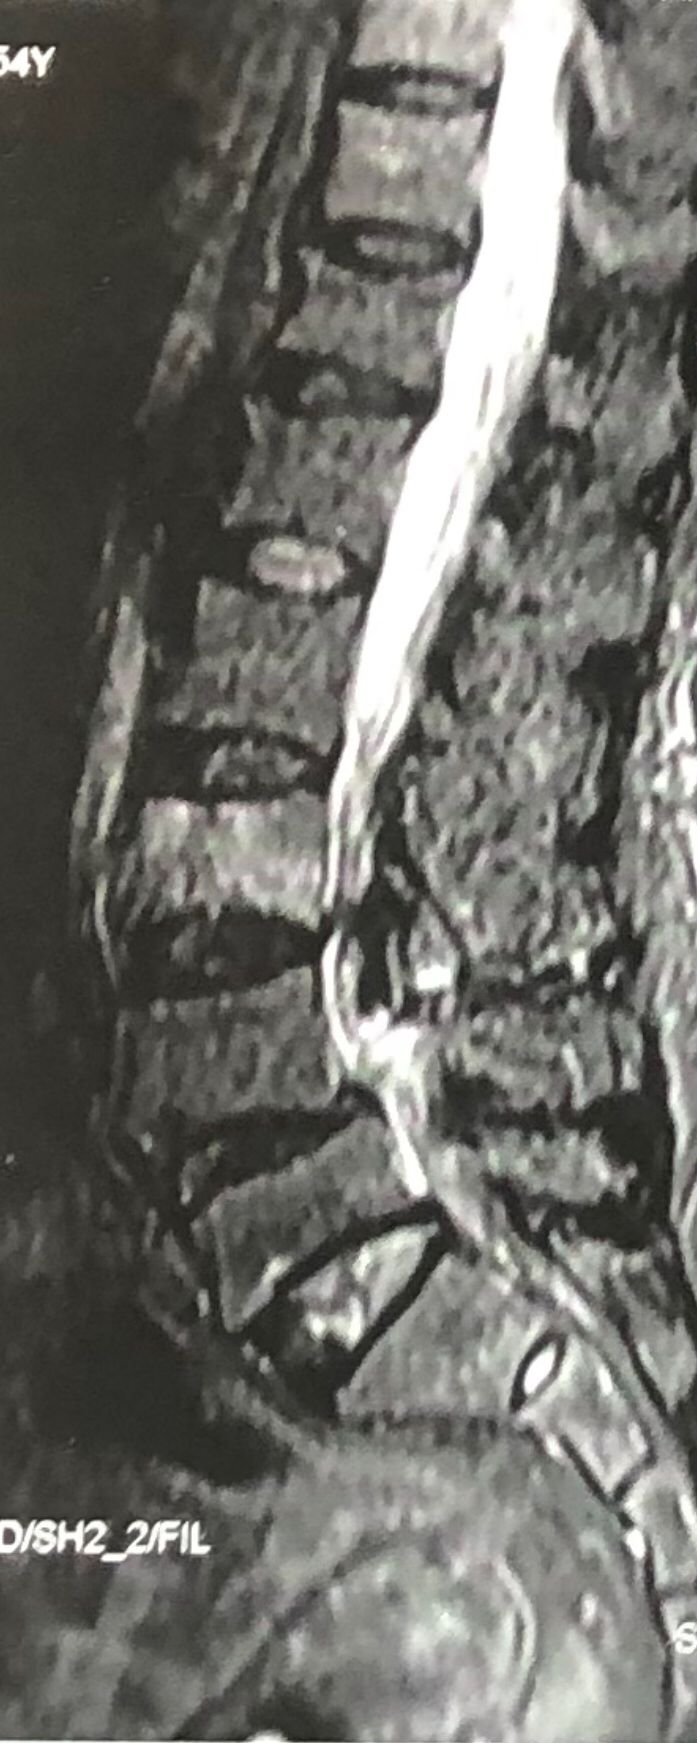

46 years old female patient presented to my clinic yesterday june 1/2025 with LBP and radicular L leg pain for several months which hasn’t responded to physio 2 neurosurgeons have visited her and didn’t suggest any surgery Neurological exam was unremarkable please see her mri/ emg/ncv and her huge tarlov cyst and possible L IVF L4-5 hyperbulge I ordered sacrum mri and ct scan and new emg/ncv and asked her with her sacral Ct scan and MRI first sees another two famous neurosurgeons and see if that large cyst is the reason for her pain if not i can work on her L4-S1 area Do you think her radicular pain can originate from her large cyst in sacrum? Do you consider surgery and removing her sacral cyst?